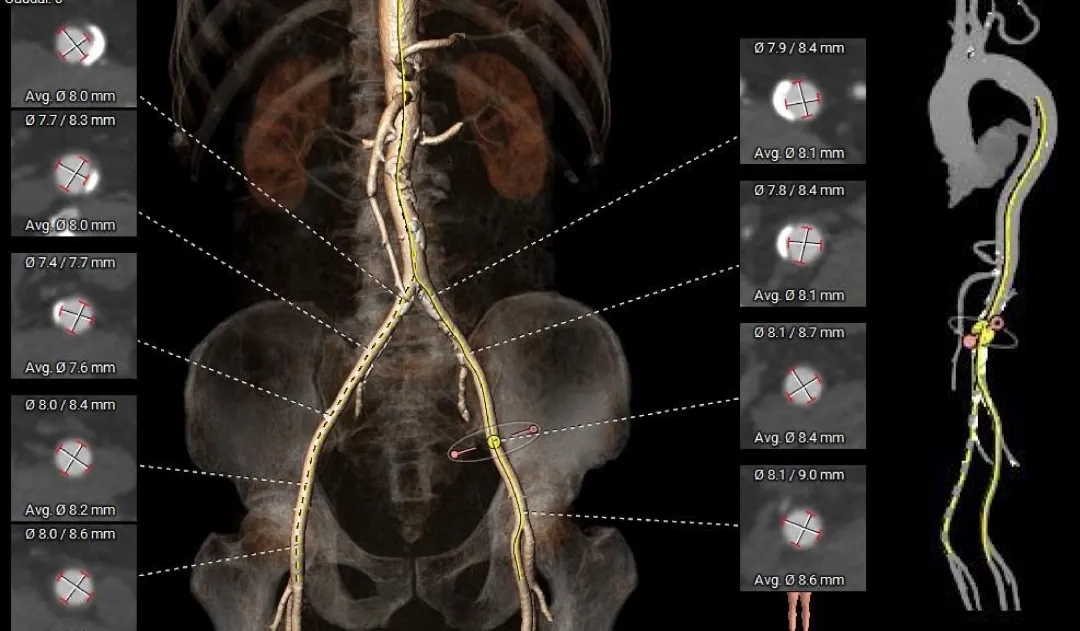

术前CT分析

主动脉根部测量

Annulus

26.6mm

LVOT

27mm

SOV

40.2*39.3*38mm

STJ

36.7mm

AAO

38.8mm

心脏角度

纯反流三叶瓣,瓣环内径26.6mm

流出道偏直筒型

瓣叶轻微增厚、无钙化

57°,近似横位心

瓣上结构测量

瓣上2mm

27.3mm

瓣上4mm

29mm

瓣上6mm

30.1mm

瓣上8mm

31.1mm

瓣上锚定空间逐渐增大,仅瓣上0-2mm可提供锚定力

外周入路评估

-

髂动脉轻微迂曲

腹主动脉可见钙化斑块

血管内径充足